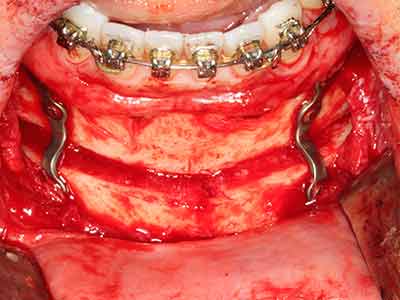

Костната тъкан е не само минерализирана структура, тя съдържа и съществено количество колагенови влакна. Това означава, че тя има не само добра компресивна сила, но и известна степен на гъвкавост, която може да се възприеме като предимство при извършване на костна аугментация. В класическата процедура по разширяване чрез костно разделяне, атрофиралият алвеоларен гребен е разделен надлъжно и внимателно разширен след достигане на подходящата остеотомна дълбочина (Фиг. 13-16), в идеалния случай без допълнително отстраняване на периостеума (Brugnami, Caiazzo et al. 2014, Stricker, Fleiner et al. 2014). Системите с винт и пластини с увеличаване на разстоянието при разширяване са доказали ефективността си при разделяне на двете костни ламели, оставайки под прага на фрактурите. В общи линии, оставащата ширина на костта от поне 3–4 mm е задължителна (Chiapasco, Zaniboni et al. 2006), за да се гарантира добра гъвкавост и достатъчно костно покритие за бъдещото поставяне на импланти. Ако е необходимо, вертикалната остеотомия на едната или двете страни може да подобри гъвкавостта. Комбинацията с допълнителни техники за аугментация, особено в букалната страна, е описана като алтернатива на класическата техника.